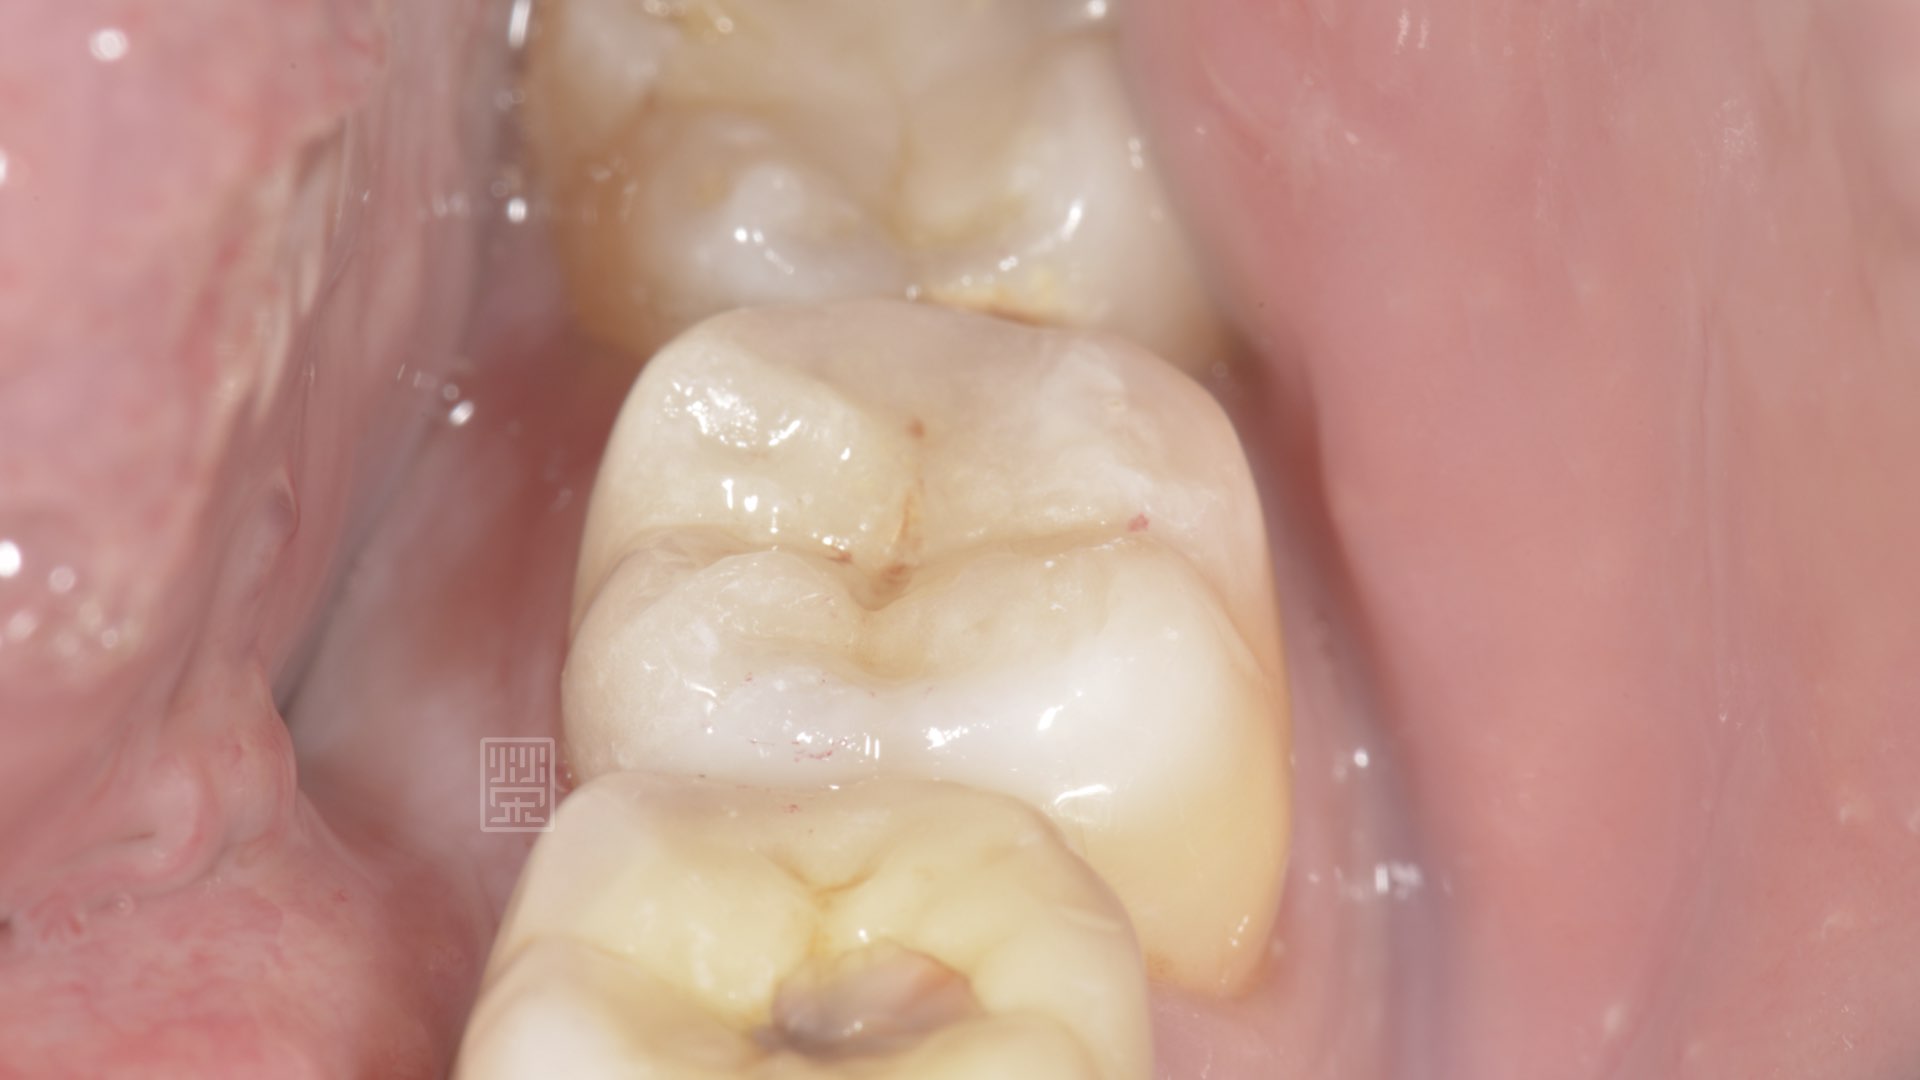

全瓷嵌體修復